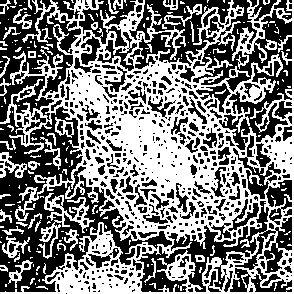

Figure 3: Original images of sequence is example of high dynamics of cell behavior affecting on contrast properties

The Fig.3 is representing couple of frames of sample image sequence with relatively high contrast between foreground and can be segmented with almost 95% accuracy with any method we used. Frame 1 of sample sequence presented at Fig.3(a) contain regions of hyper contrast pixels. In this case such condition does not affect on valid recognition since they are belong to object and present on margins of it and differs well from background. For Frame 2 there is absence of such pixels (Fig.3(b)) and this conditions also makes segmentation possible in relatively inflexible filtering conditions. The Frame 2 has relatively low contrast however it is seen that after filtration applied on image we achieve good difference of core and cell body compared to background as it presented at Fig.4 .